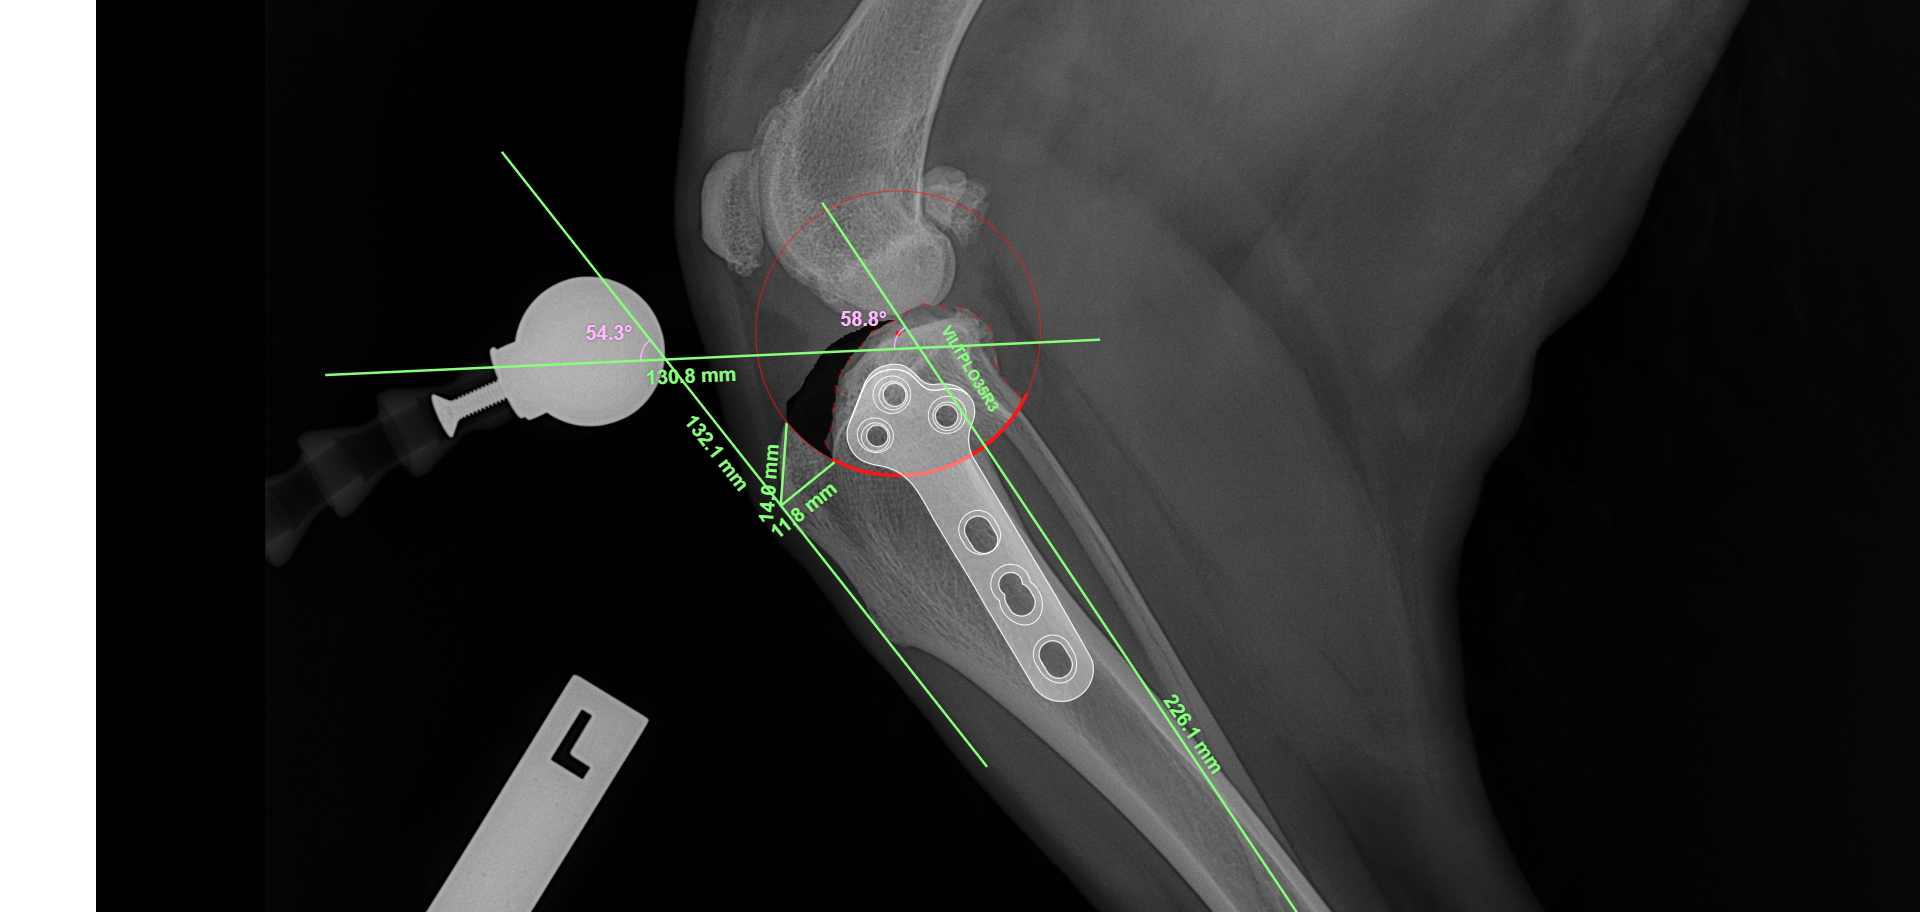

Our experienced small animal veterinary surgeons can offer a complex surgery service in the local area. We are also taking advanced surgical referrals for other local practices in the Central Coast, Lake Macquarie, Newcastle, and beyond. Complex surgeries currently being offered include: spinal surgery (spinal decompression), fracture repair (plating and pinning), limb amputation, joint fusion (arthrodesis), angular limb correction, total hip replacements (THR), patella luxation surgery (MPL), cruciate ligament repair (Tibial Plateau Levelling Osteotomy - TPLO, Tibial Tuberosity Advancement - TTA, DeAngelis procedure), and many others.

Each surgery is supported by thorough pre-anaesthetic testing, tailored pain relief and ongoing post-operative monitoring. If your pet is limping, reluctant to move or showing signs of discomfort, a consultation may help determine the next steps. We also work in conjunction with our diagnostic services, medical testing and recovery planning to provide integrated care throughout the process.